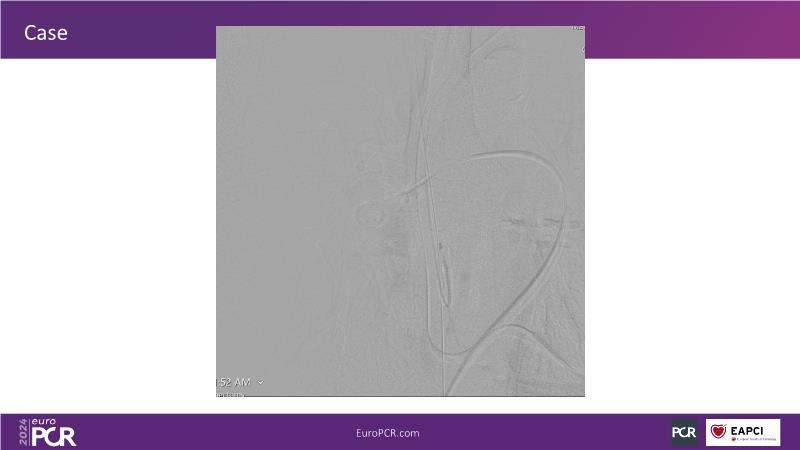

Join this session to delve into innovations in computer-assisted vacuum thrombectomy for acute pulmonary embolism, leveraging real-life case scenarios to share practical experiences and discuss treatment strategies. Amidst the current surge in scientific research, ongoing trials like STORM PE and STRIKE PE are pivotal in shaping the landscape of pulmonary embolism management.

- To share practical experience using real-life case scenarios